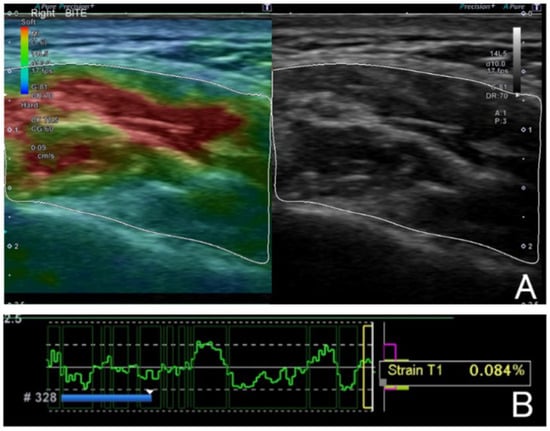

Evaluation of Strain Values for Masseter Muscle Activity of Dentofacial Deformities Using Ultrasound Elastography

by Yutaka Sasajima, Kazuhiro Ooi, Takako Terakami, Rei Jokaji, Hirokazu Okita, Yusuke Nakade and Shuichi Kawashiri

J. Clin. Med. 2025, 14(21), 7769; https://doi.org/10.3390/jcm14217769 - 1 Nov 2025

Background/Objective: This study aimed to evaluate the strain values (SVs) of masseter muscle activity in dentofacial deformities (DDs) using ultrasound elastography. Methods: The DD group consisted of 60 patients with dentofacial deformities with skeletal class II or III malocclusion, and the [...] Read more.

Background/Objective: This study aimed to evaluate the strain values (SVs) of masseter muscle activity in dentofacial deformities (DDs) using ultrasound elastography. Methods: The DD group consisted of 60 patients with dentofacial deformities with skeletal class II or III malocclusion, and the control group consisted of 26 volunteers with normal occlusion. The SVs and the cross-sectional area of the masseter muscle were measured using an ultrasonic elastography. These were measured at three functional positions: resting, mouth opening, and clenching. The SVs were statistically compared with the DD and control groups. Changes in the cross-sectional area and factors (patient status, skeletal morphology, and oral function) related to the SVs in the study group were statistically analyzed. Results: The SVs were significantly higher during clenching than in resting and mouth opening in both groups, although there was no correlation between the DD group and the control group. The cross-sectional area was larger during clenching, resting, and mouth opening. The resting SVs decreased as the masseter muscle cross-sectional area increased. The SVs of clenching increased with higher resting SVs and decreased with greater maximum mouth opening. Conclusions: The SVs measured by ultrasound elastography changed depending on functional mandibular movement and have the potential to evaluate the masseter muscle activity of dentofacial deformities. Full article